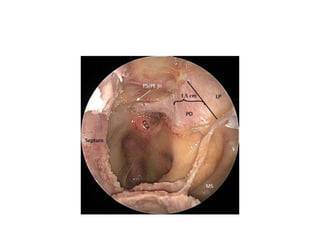

HADAD FLAP ---1, area

of origin of the nasoseptal flap (dotted line); 1b, area of origin of the

extended nasoseptal flap, including the floor of the nasal fossa, and if

necessary, the mucosa of the inferior meatus; 2, position of the nasoseptal

flap used for repair of the anterior and posterior ethmoid roof and

cribriform plate; when bilateral flaps are taken, the anterior skull base

can be repaired from orbit to orbit; 3, position of the nasoseptal flap

used for repair of the sellar and parasellar regions; 4, position of the nasoseptal

flap used for repair of the region of the clivus; the arrows indicate

the different ways in which the nasoseptal flap (HBF) can be rotated

from the nasal septum for repair of different zones of the cranial base.